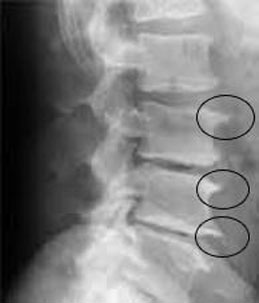

As dores ciáticas geralmente são iniciadas por hérnias de disco, espondiloartroses que é artrose (desgaste ósseo) na coluna, que por vezes geram os osteofitos (bicos de papagaio) e que agem como agente estressor da raiz do nervo, assim como a hernia de disco. Se algo incomoda a raiz de qualquer um dos 4 nervos descritos acima como originarios do nervo ciatico os sintomas podem aparecer.